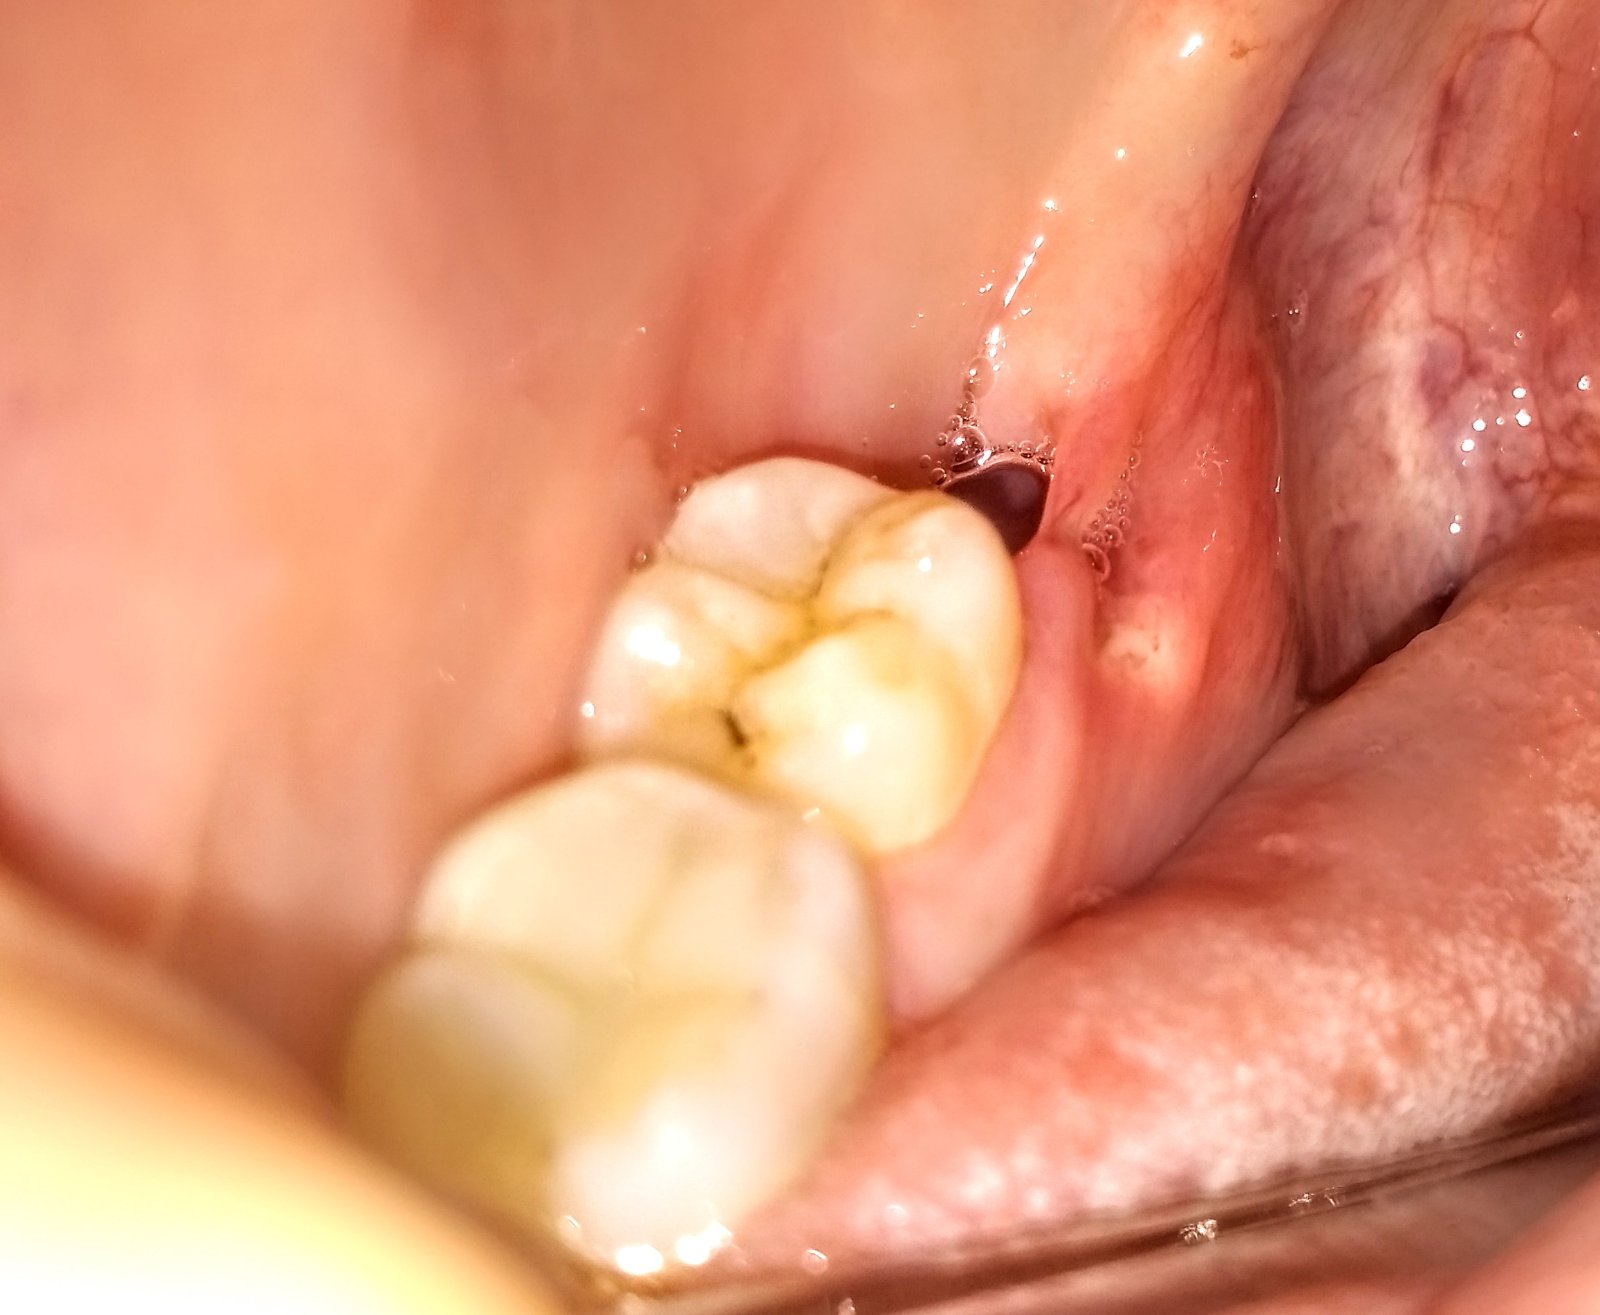

Zdravim, pred 3 týždňami mi trhali osmičku. Veľmi bolestivý zákrok aj samotné hojenie. Ešte stále ma rána bolí. Do toho sa mi spravilo vedľa rany niečo takéto biele. Bolí to, bolí ma z toho jazyk aj ústa. Na dotyk lyžičkou je to tvrdé. Tak mi napadlo, či to nemôže byť kosť, čo sa dostala na povrch pri sťahovaní ďasna. Stalo sa to niekomu z vás? Ak áno, trochu ma to upokojí. Zubárovi môžem ísť až v stredu. Ďakujem za radu.

Ďakujem všetkým za povzbudenia a rady. Išla som teda na pohotovost. Je to kosť, čo sa dostala von cez tenké ďasno. Tam ho narezali a zostalo tenké. Vraj suchanim jazyka a možno aj medzizubnou kefkou, ktorou som sa snažila očistiť vedľajší zub sa ďasno pretrhlo a vyšla von kost. Ale dobrá správa - zahojí sa to vraj samé, len to chce čas, ďasno ju prerastie. Ešte mi dali odporúčanie nečistit si ranu (ani po takom dlhom čase od zákroku), potrava, ktorá sa tam dostane sa sama z rany vylúči.